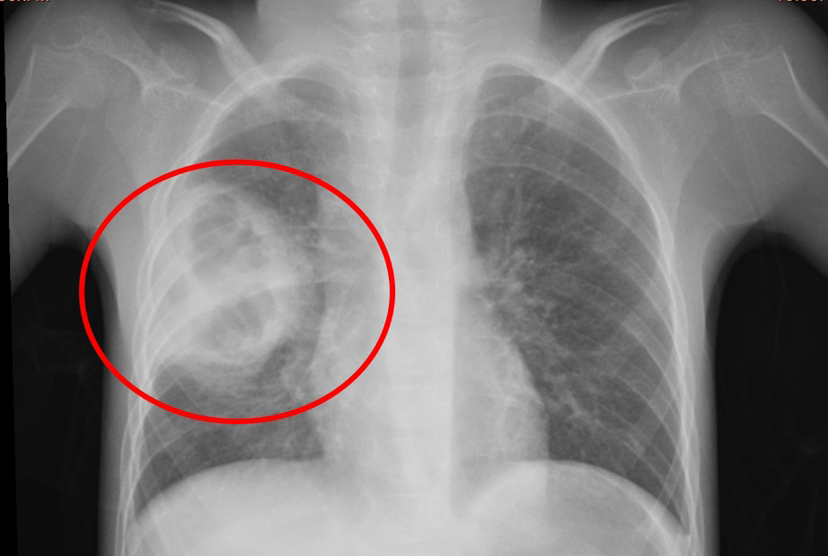

近日,重庆医科大学附属璧山医院(重庆市璧山区人民医院)儿科历经40余天的精心治疗与护理,成功点亮了一名因肺部重度感染并发肺脓肿、病情极其危重的脑瘫患儿的“生命之光”。